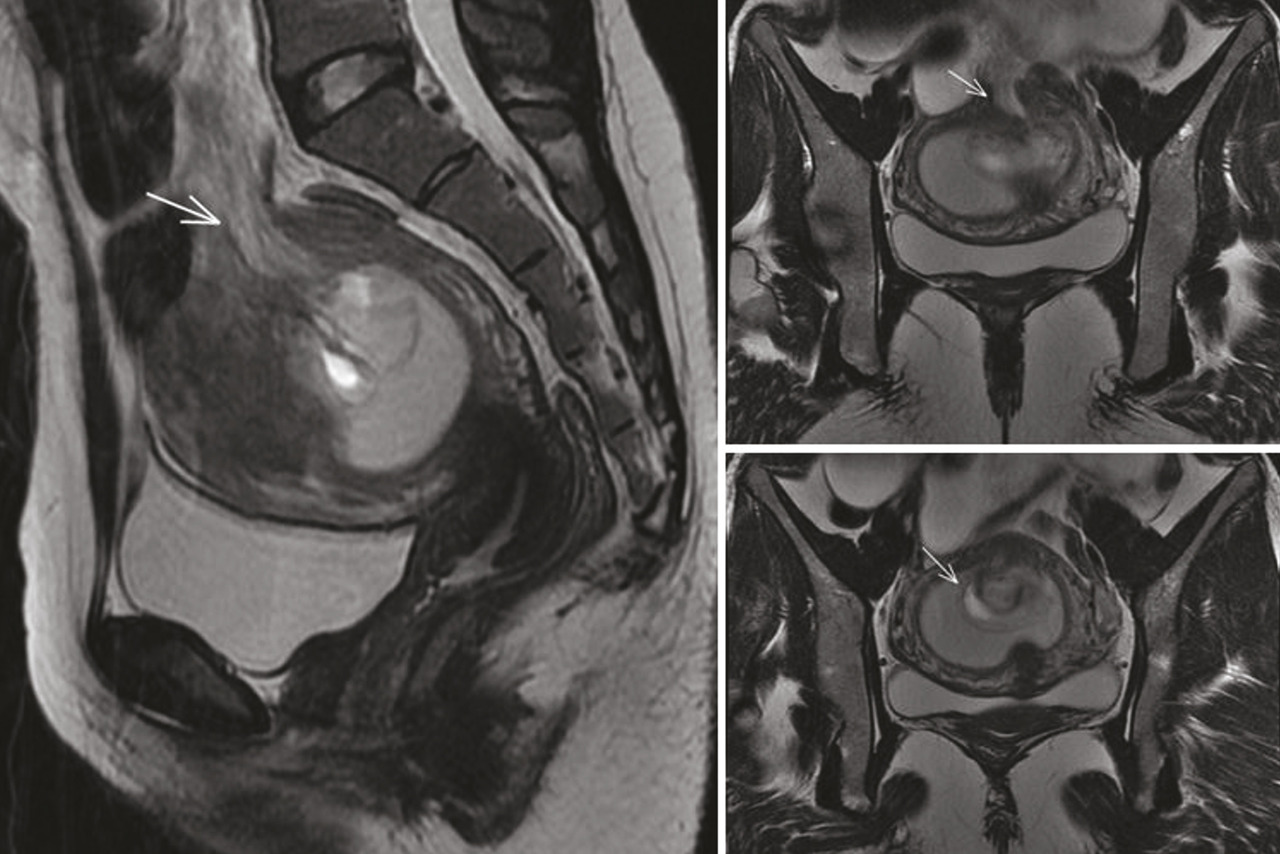

Le scanner (fig. 1 ) et l’imagerie par résonance magnétique (IRM) [fig. 2 ] montrent un défect pariétal du fond utérin avec incarcération d’une anse intestinale en position intra-utérine qui semble discontinue, avec un contenu hématique en hypersignal T1 et une distension de l’intestin grêle d’amont à contenu hydro-aérique, ainsi qu’un épanchement liquidien intrapéritonéal.

Le scanner (